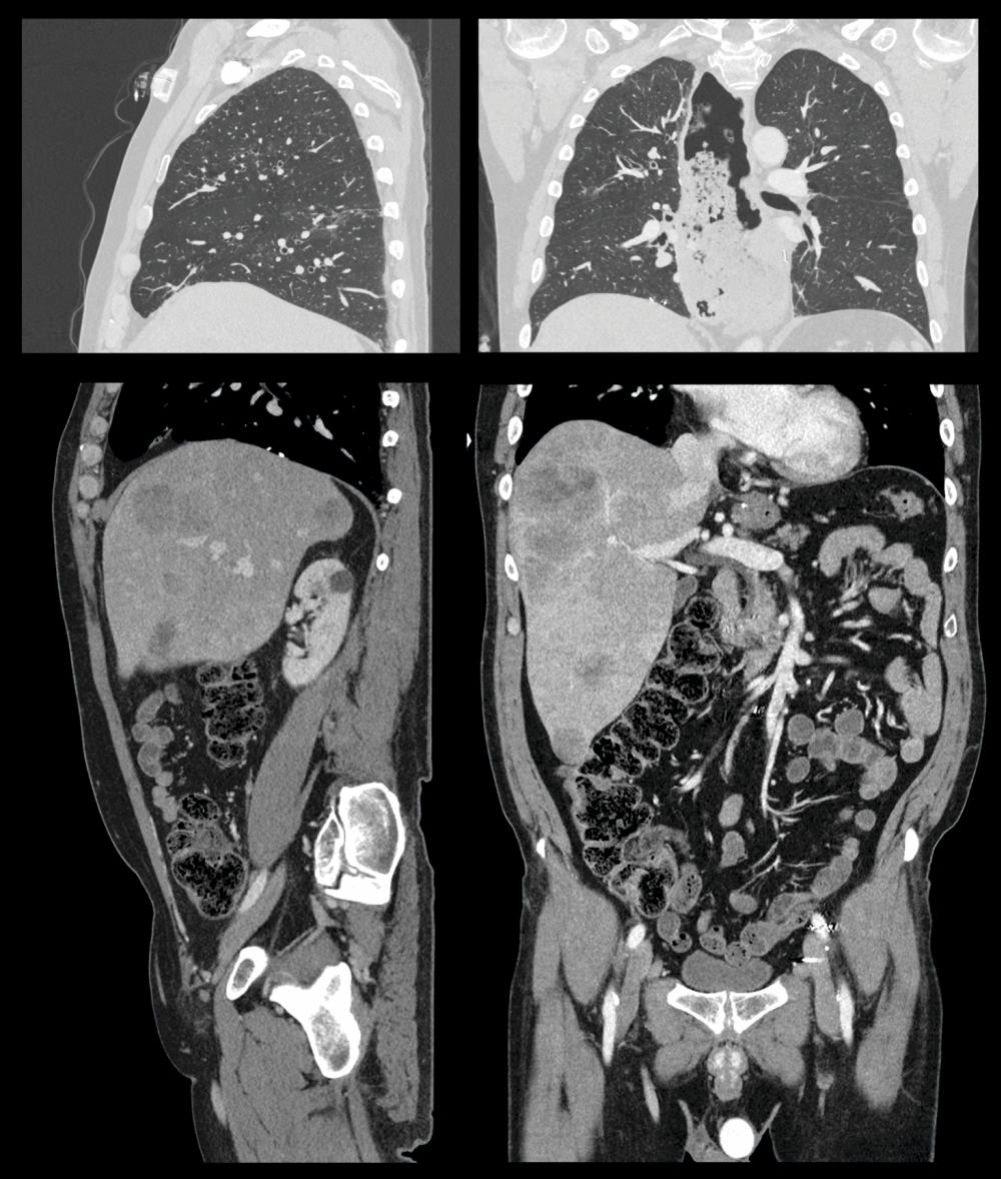

Figure 2.

Sagittal and coronal perspectives of the torso. Images of the thorax (top) and abdomen and pelvis (bottom) demonstrate the remarkable clarity with which computed tomography (CT) imaging can depict human anatomy. Excellent contrast between air, tissue, and bone makes CT scans of the lung essential for diagnosing many pulmonary disorders. A vascular contrast agent containing high-atomic-number iodine can be injected to enhance the contrast of soft tissues in the abdomen and pelvis and make blood vessels and cardiac chambers visible. (Courtesy of Canon Medical Systems, USA.)